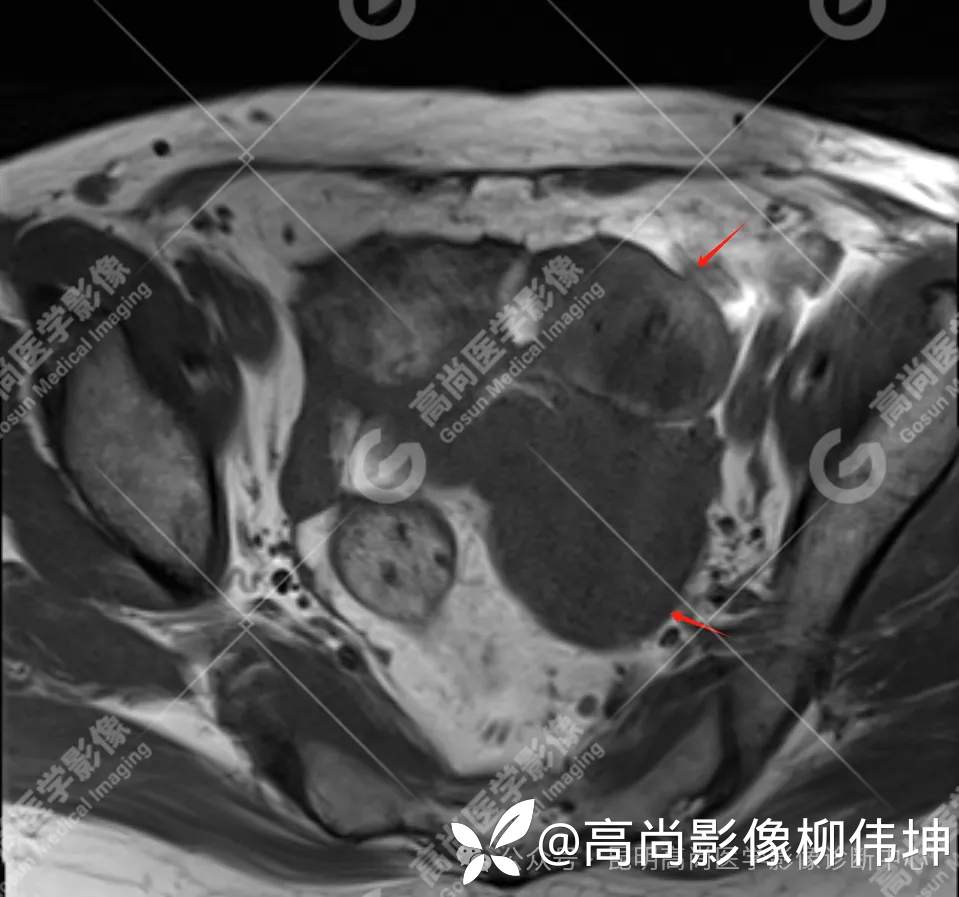

T2WI-tra

(2)MRI表现:通常双侧发生,体积巨大,呈外生性、囊实性、乳头状生长,其内见大量长T1长T2液性信号影及线性分隔,囊壁厚薄不均,可见壁结节及不同比例实性成分,呈T1等信号,T2略高信号。扩散受限,DWI呈高信号,ADC呈低信号。增强扫描实性成明显强化。另外,常可检出腹水、腹膜增厚、盆壁及盆腔脏器受累、淋巴结肿大等表现。